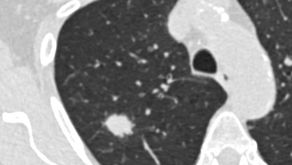

Früherkennung von Lungenkrebs: Zusätzliche Kriterien könnten mehr Fälle aufdecken

[Mitglieder-Bericht 146/2025, Lübeck/Berlin/Hannover, Freitag, 14.11.2025] Um die hohe Sterblichkeitsrate bei Lungenkrebs zu senken, soll in Deutschland ein Früherkennungsprogramm eingeführt werden. Es richtet sich an Menschen ab 50, die lange stark geraucht haben.